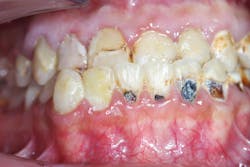

No. 3: Mandibular arch

- Followed same protocol

- Final lithium disilicate restorations (IPS e.max; figure 3)